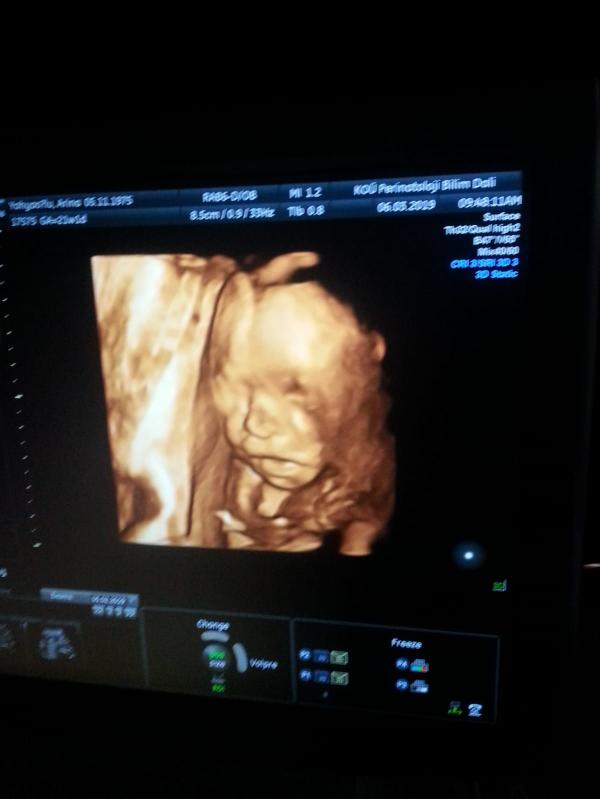

Ну вот сегодня сходили на УЗИ. после амнио прошел ровно месяц. С моим сыночком все в порядке. Пошла 22 неделя беременности. По УЗИ вес установили 440 грамм. Это вроде как крупнячок.

Во время обследования вертелся - чёткой фоточки не получилось.

УЗИ проводили в университетской клинике КОДЖАЭЛИ Измит. Я просто попросила фоточку и мне не отказали. Ни копейки не платили за 3д фото.

@narisha_lara да, профессор смотрел полчаса - каждый орган и каждую часть тела на предмет отклонений. Никаких проблем не выявлено.